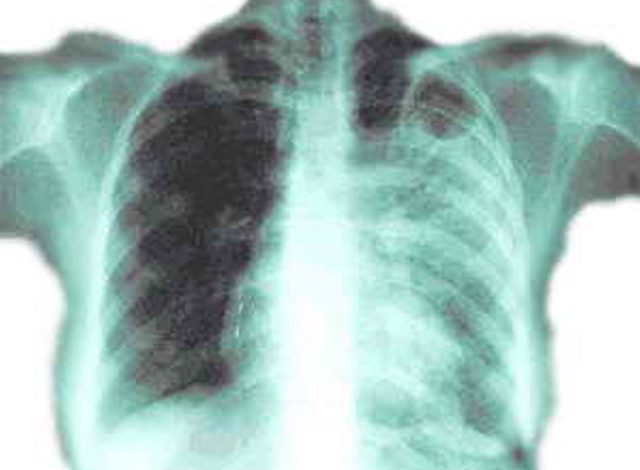

Валецький зазначає: особливістю туберкульозу є те, що він локалізується не лише в легенях, як усі звикли думати, а може уражати всі без винятку органи.